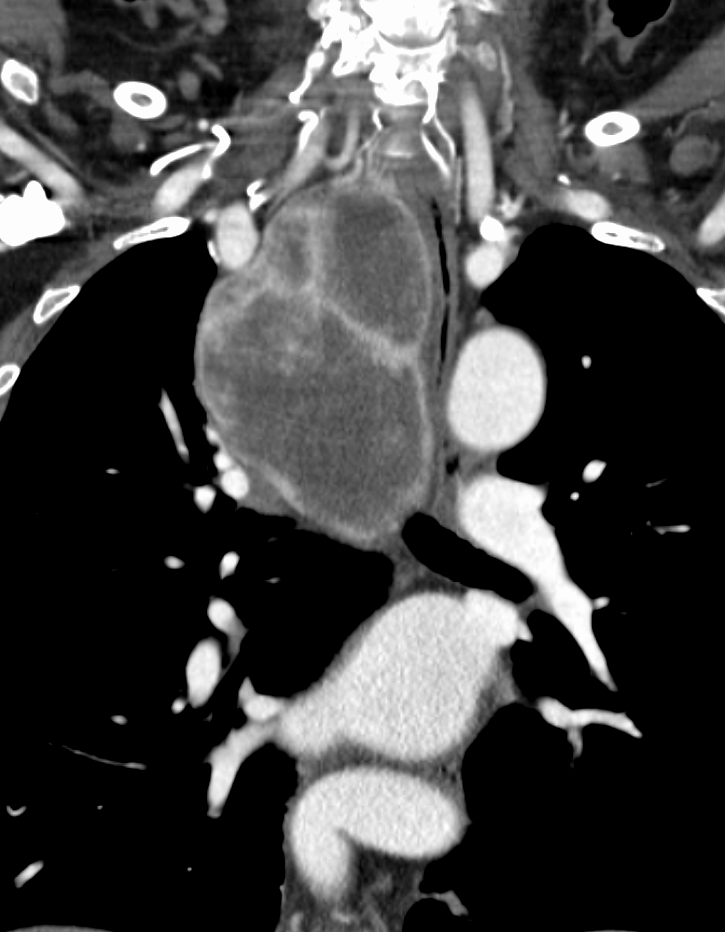

胸腔鏡による低侵襲手術の一方では、大動脈や気道への浸潤が疑われるような高度進行食道がんに対しても、総合外科学講座の利点を最大に生かして、心臓血管外科、呼吸器外科、形成外科の先生方に協力を頂き、手術適応を十分に検討したうえで他臓器合併切除などの拡大手術にも取り組んでいます。

縦隔内甲状腺腫

呼吸器外科合同による胸腔鏡手術と頸部手術

中毒性甲状腺腫

ECMO下に甲状腺全摘術を施行